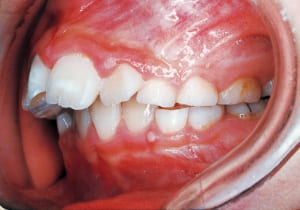

2 After Phase 2 Treatment 6-6-’94

The first phase of treatment involved extracting the left and right maxillary deciduous canines. The space created was used to forcibly retract the four anterior teeth, thereby aiming to improve lip closure function (6–9, 11). Morphological changes suggest that lip function differed before and after treatment (6, 9). Subsequently, the first premolars erupted, but extraction is planned to secure space for canine eruption (10). A Class II molar relationship remains, but the significant overjet has improved (11).

In the maxilla, insufficient space for canine eruption was inevitable, necessitating extraction as part of the treatment plan. The maxillary first premolars on both sides were extracted during routine observation to create space for canine eruption (14). Eventually, the canines erupted and settled into relatively favorable positions (15,19,20). In the mandibular dentition, crowding was also present, leading to extraction of the mandibular first premolars on both sides. Treatment with full bracket was then initiated (17).